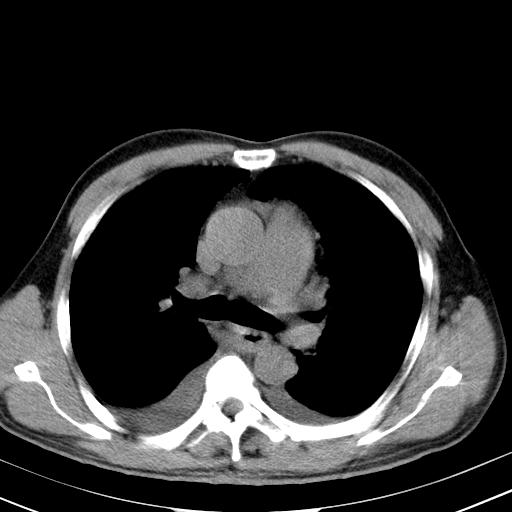

以下是引用zjzjr在2010-3-21 17:39:00的发言:[br]右下中心型肺癌并阻塞性肺炎/不张,纵膈淋巴结肿大,右侧大量胸腔积液,左侧少量胸腔积液

以下是引用zxl51642在2010-3-21 17:06:00的发言:[br]右下中心型肺癌并阻塞性肺炎/不张,纵膈淋巴结肿大,右侧大量胸腔积液,左侧少量胸腔积液,少量腹水。建议纤维支气管镜进一步检查。